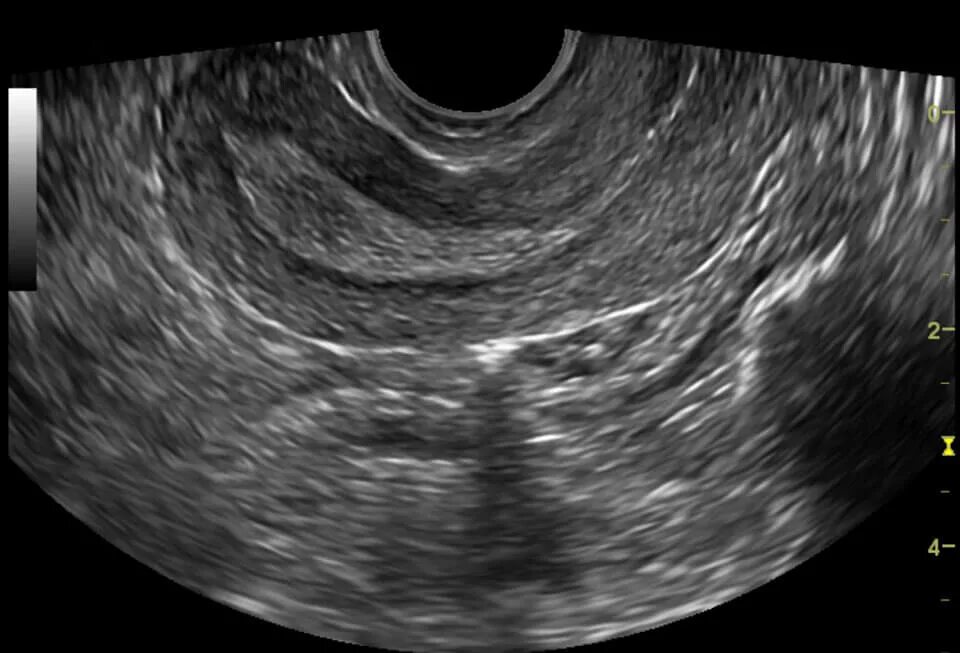

Эндометрий 9 мм